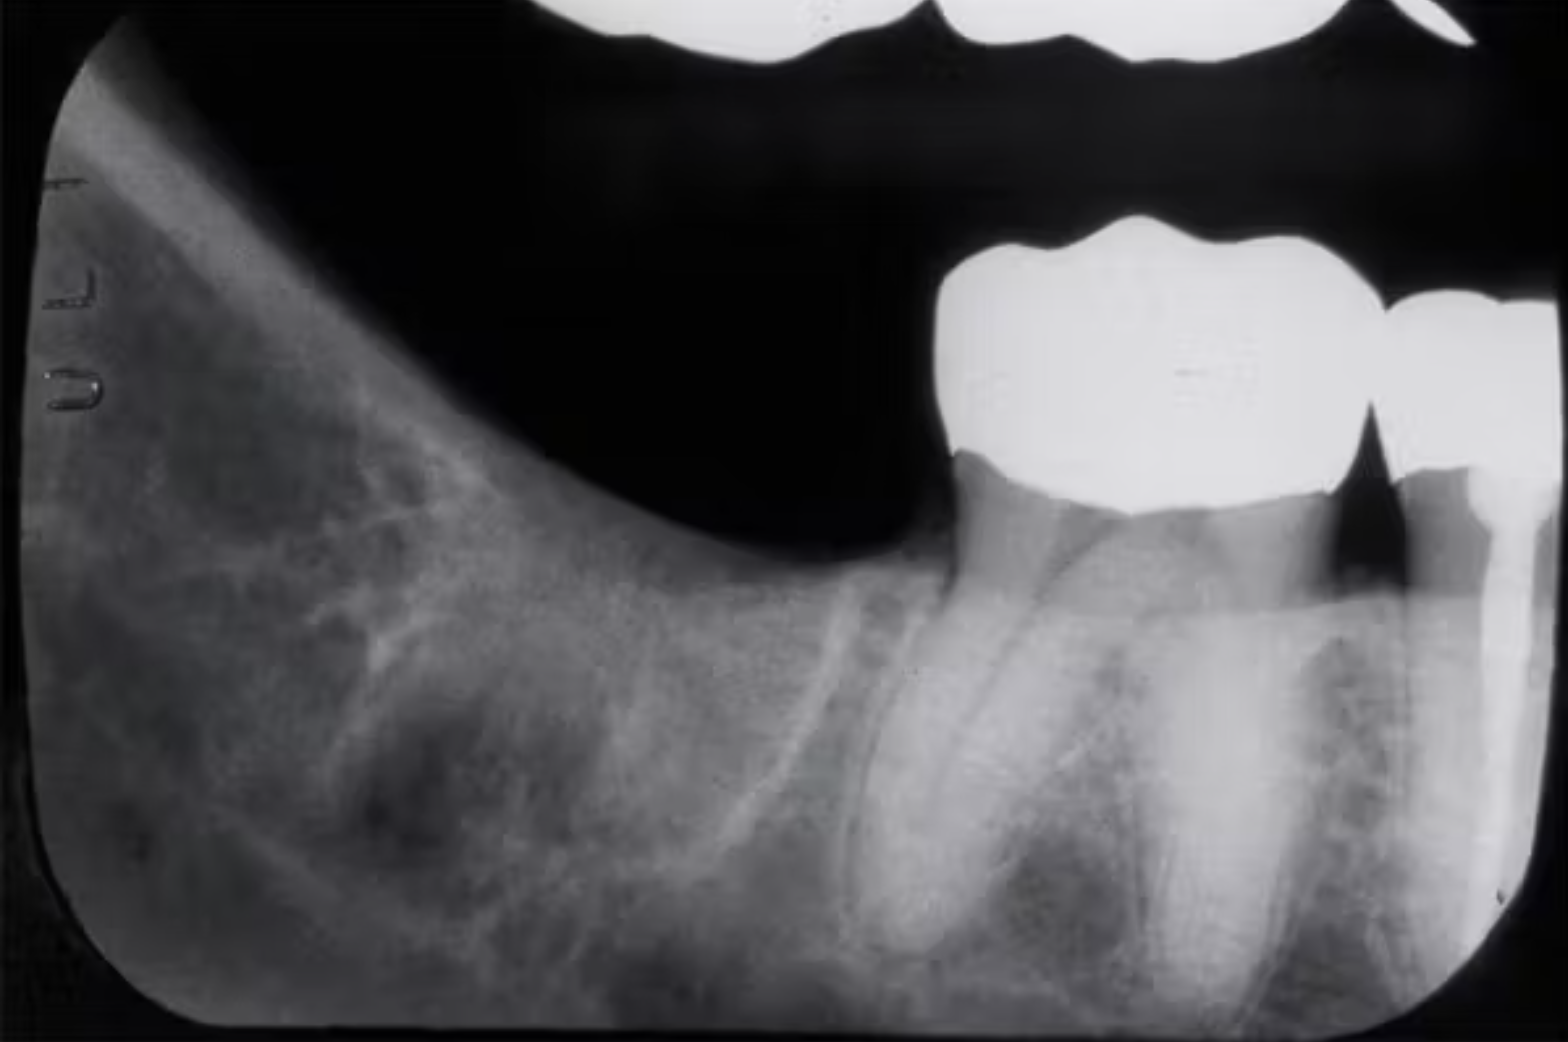

Khi chụp X-quang, bác sĩ có thể nhận thấy một hình dạng giống như ổ chân răng ở vùng đã nhổ, thường là nhiều năm sau khi bệnh nhân có than phiền (Hình 1 và 2). Đây được gọi là ổ chân răng sót lại (residual root socket). Đường viền của ổ chân răng vẫn mờ mờ nhìn thấy, và khi thăm khám phẫu thuật, vùng này có thể rỗng hoặc được lấp đầy bởi mô sẹo xơ đặc, mô hạt hoặc xương non chưa trưởng thành.

(Hình 2: Ổ chân răng sót lại ở hàm dưới bên trái – Nguồn: Dr. Jerry E. Bouquot.)